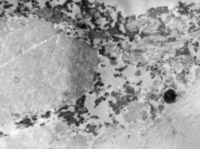

5-2-8 傷后第10天,皮膚附件上皮細胞成簇分布,核仁邊集,內(nèi)質(zhì)網(wǎng)擴張,胞質(zhì)內(nèi)含較多張力原纖維  TEM×6000